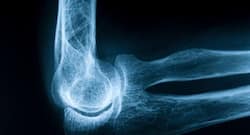

Bone Health: Signs And Symptoms You Have Weak Bones But Not Osteoporosis

Just because you do not have osteoporosis, it does not mean your bones are in perfect shape. If you are noticing any warning signs, DO NOT ignore them!

"A healthy lifestyle is your best prevention against chronic diseases like osteoporosis." says Dr. Aashish Chaudhry, Senior Consultant & Head, Department of Orthopaedics & Joint Replacement, Aakash Healthcare.